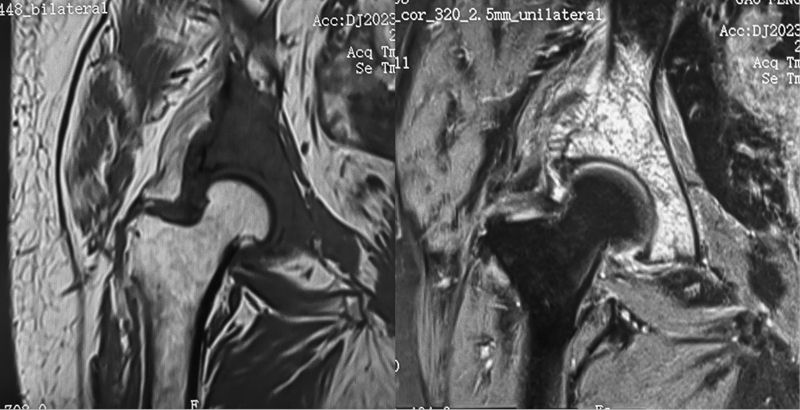

图2a 女,68岁,直肠癌术后系统化疗和靶向治疗近5年。MR显示T1WI示右侧髋臼见片状模糊低信号骨破坏,T2WI压脂病变呈较明显高信号,外侧骨皮质破坏、毛糙,见细小垂直状骨膜增生,考虑直肠癌髋臼转移